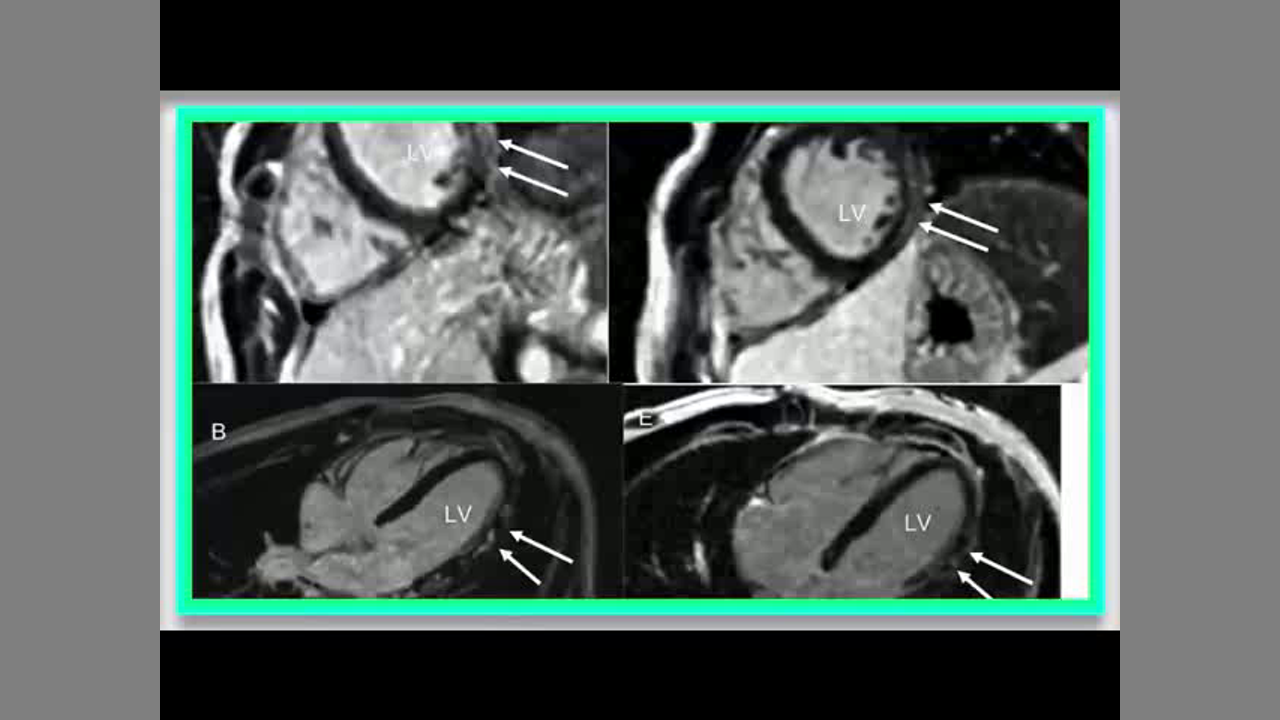

Myopericarditis, has emerged as an important adverse event following COVID-19 mRNA vaccination, particularly in adolescents. Patients typically exhibit chest pain and an elevated serum troponin level in the days following the COVID-19 mRNA vaccine. They usually are hemodynamically stable, and symptoms and cardiac biomarkers normalize within a few days. Cardiac magnetic resonance studies, when performed early, frequently demonstrate abnormalities such as edema and late gadolinium enhancement (LGE), meeting Lake Louise Criteria for diagnosing myocarditis noninvasively.